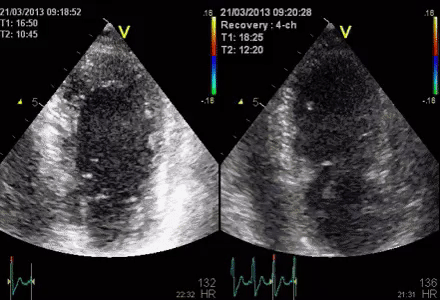

Stoyanova, Hug зарежи кечиста ... виж каква подсказка имаме от Биранд:flushed:

Малко старичък ултразвук ... от 21 март 2013, но май и нашите ГГ ще работят на тази тема..., а  колко ли ще чакаме...Wink

Специалистите казаха, че е запис на сърдечен мускул...Confused очакват ни вълнения...Kissing Smiling Eyes

Класирах се... Да не би Лейля да е бременна с този ултразвук

Сега прочетох сърдечен мускул, Нихат бей?

Или емоциите ще предизвикат сърдечни вълнения Crazy